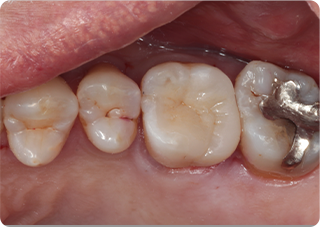

セラミックアンレー症例②

術前

むし歯除去&IDS

ラバーダム防湿

術後

| 主訴 | 右下奥歯の銀歯を白くしたい |

|---|---|

| 治療期間/回数 | 2週間、2回 |

| 価格(税込) | 143,000円(税込) |

| リスク・副作用 | セラミックの破損、一時的な知覚過敏が生じる場合がある |

| ポイント | 銀歯の中はむし歯になっていた。金属イオンにより歯の内部に黒い部分があるが、むし歯を染め出すう蝕検知液を使用し、選択的にむし歯のみを除去。また、セラミック装着時にラバーダム防湿を行うことで、詰め物の接着効果を最大限発揮できるようにした。 |